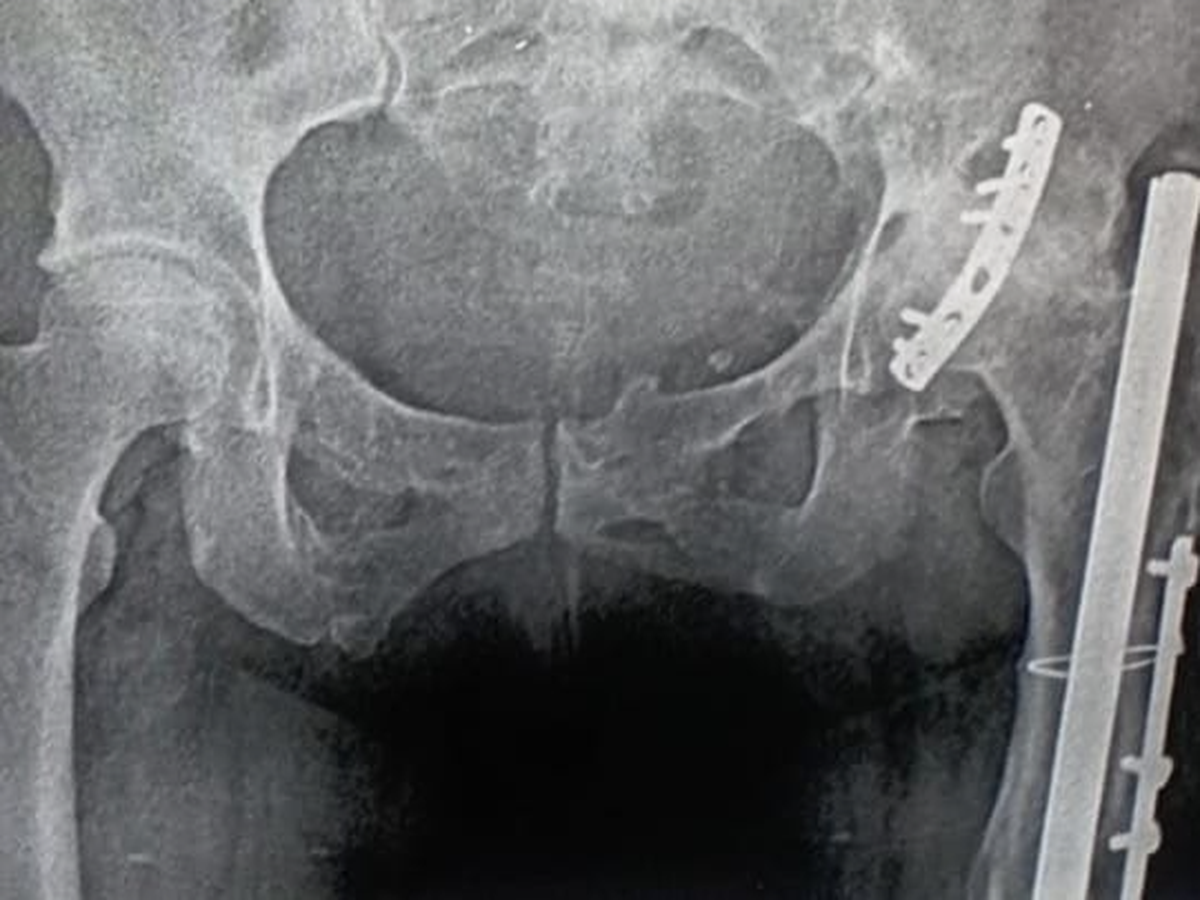

Hace algunos años, sufrí una fractura de cadera que fue tratada mediante la colocación de una placa de osteosíntesis. Con el paso del tiempo, la degeneración ósea ha avanzado y ahora los médicos indican que necesito un reemplazo de cadera. Este procedimiento consiste en la implantación de una prótesis de doble movilidad atornillada, con cabeza de cerámica, para asegurar una mayor estabilidad y durabilidad.